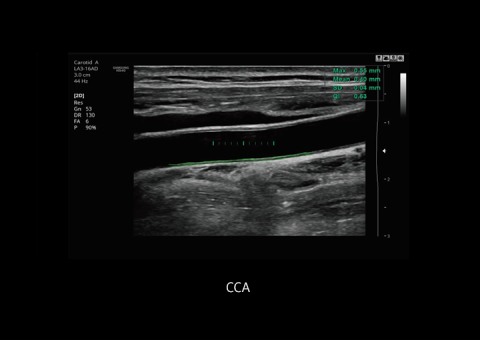

AutoIMT+ is a screening tool to analyze a patient's potential risk of cardiovascular disease. It allows easy intima-media thickness measurement of both the anterior and posterior wall of the common carotid by the click of a button.